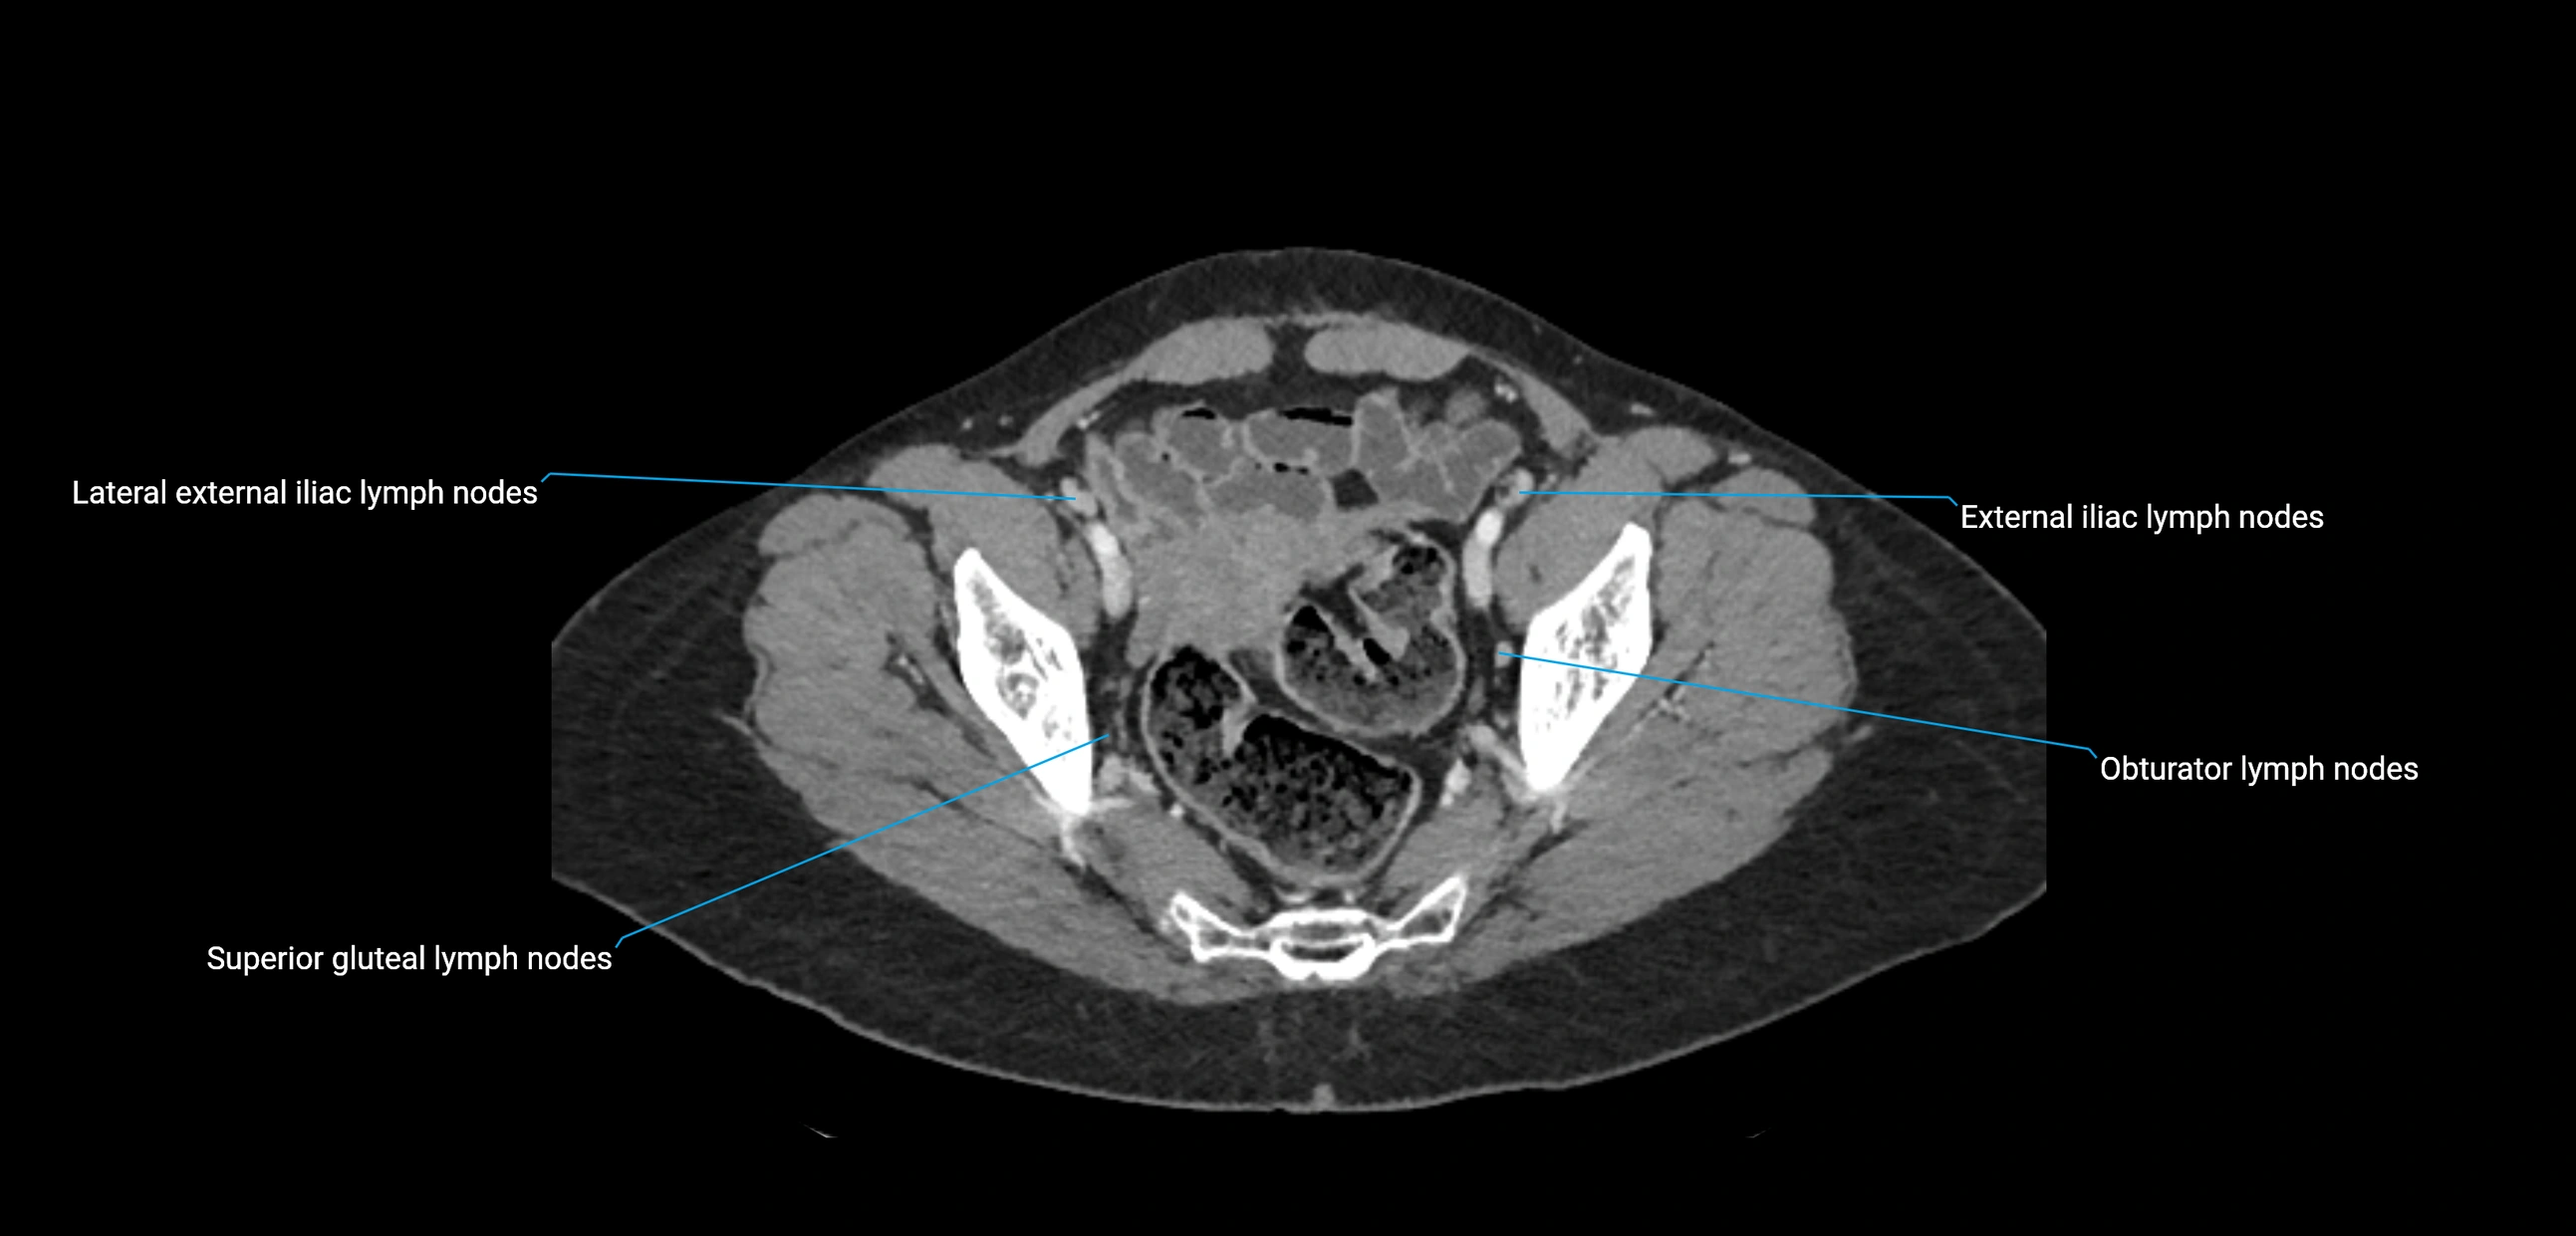

CT Appearance

CT Pre-Contrast:

• Nodes appear as soft-tissue density nodules adjacent to the aorta and IVC

• Calcification may be seen in chronic infections (e.g., tuberculosis)

CT Post-Contrast:

• Normal nodes enhance homogeneously

• Malignant nodes may show heterogeneous enhancement, central necrosis, or conglomerate formation

• Size >1 cm short axis is suspicious, though morphology and distribution are equally important